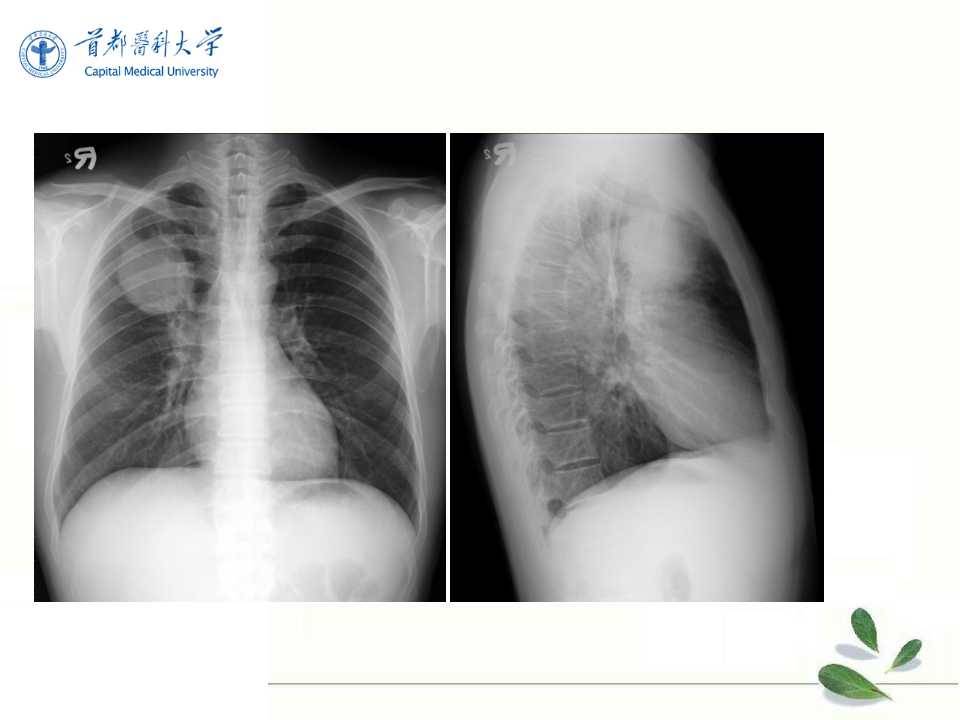

肺癌的影像学检查